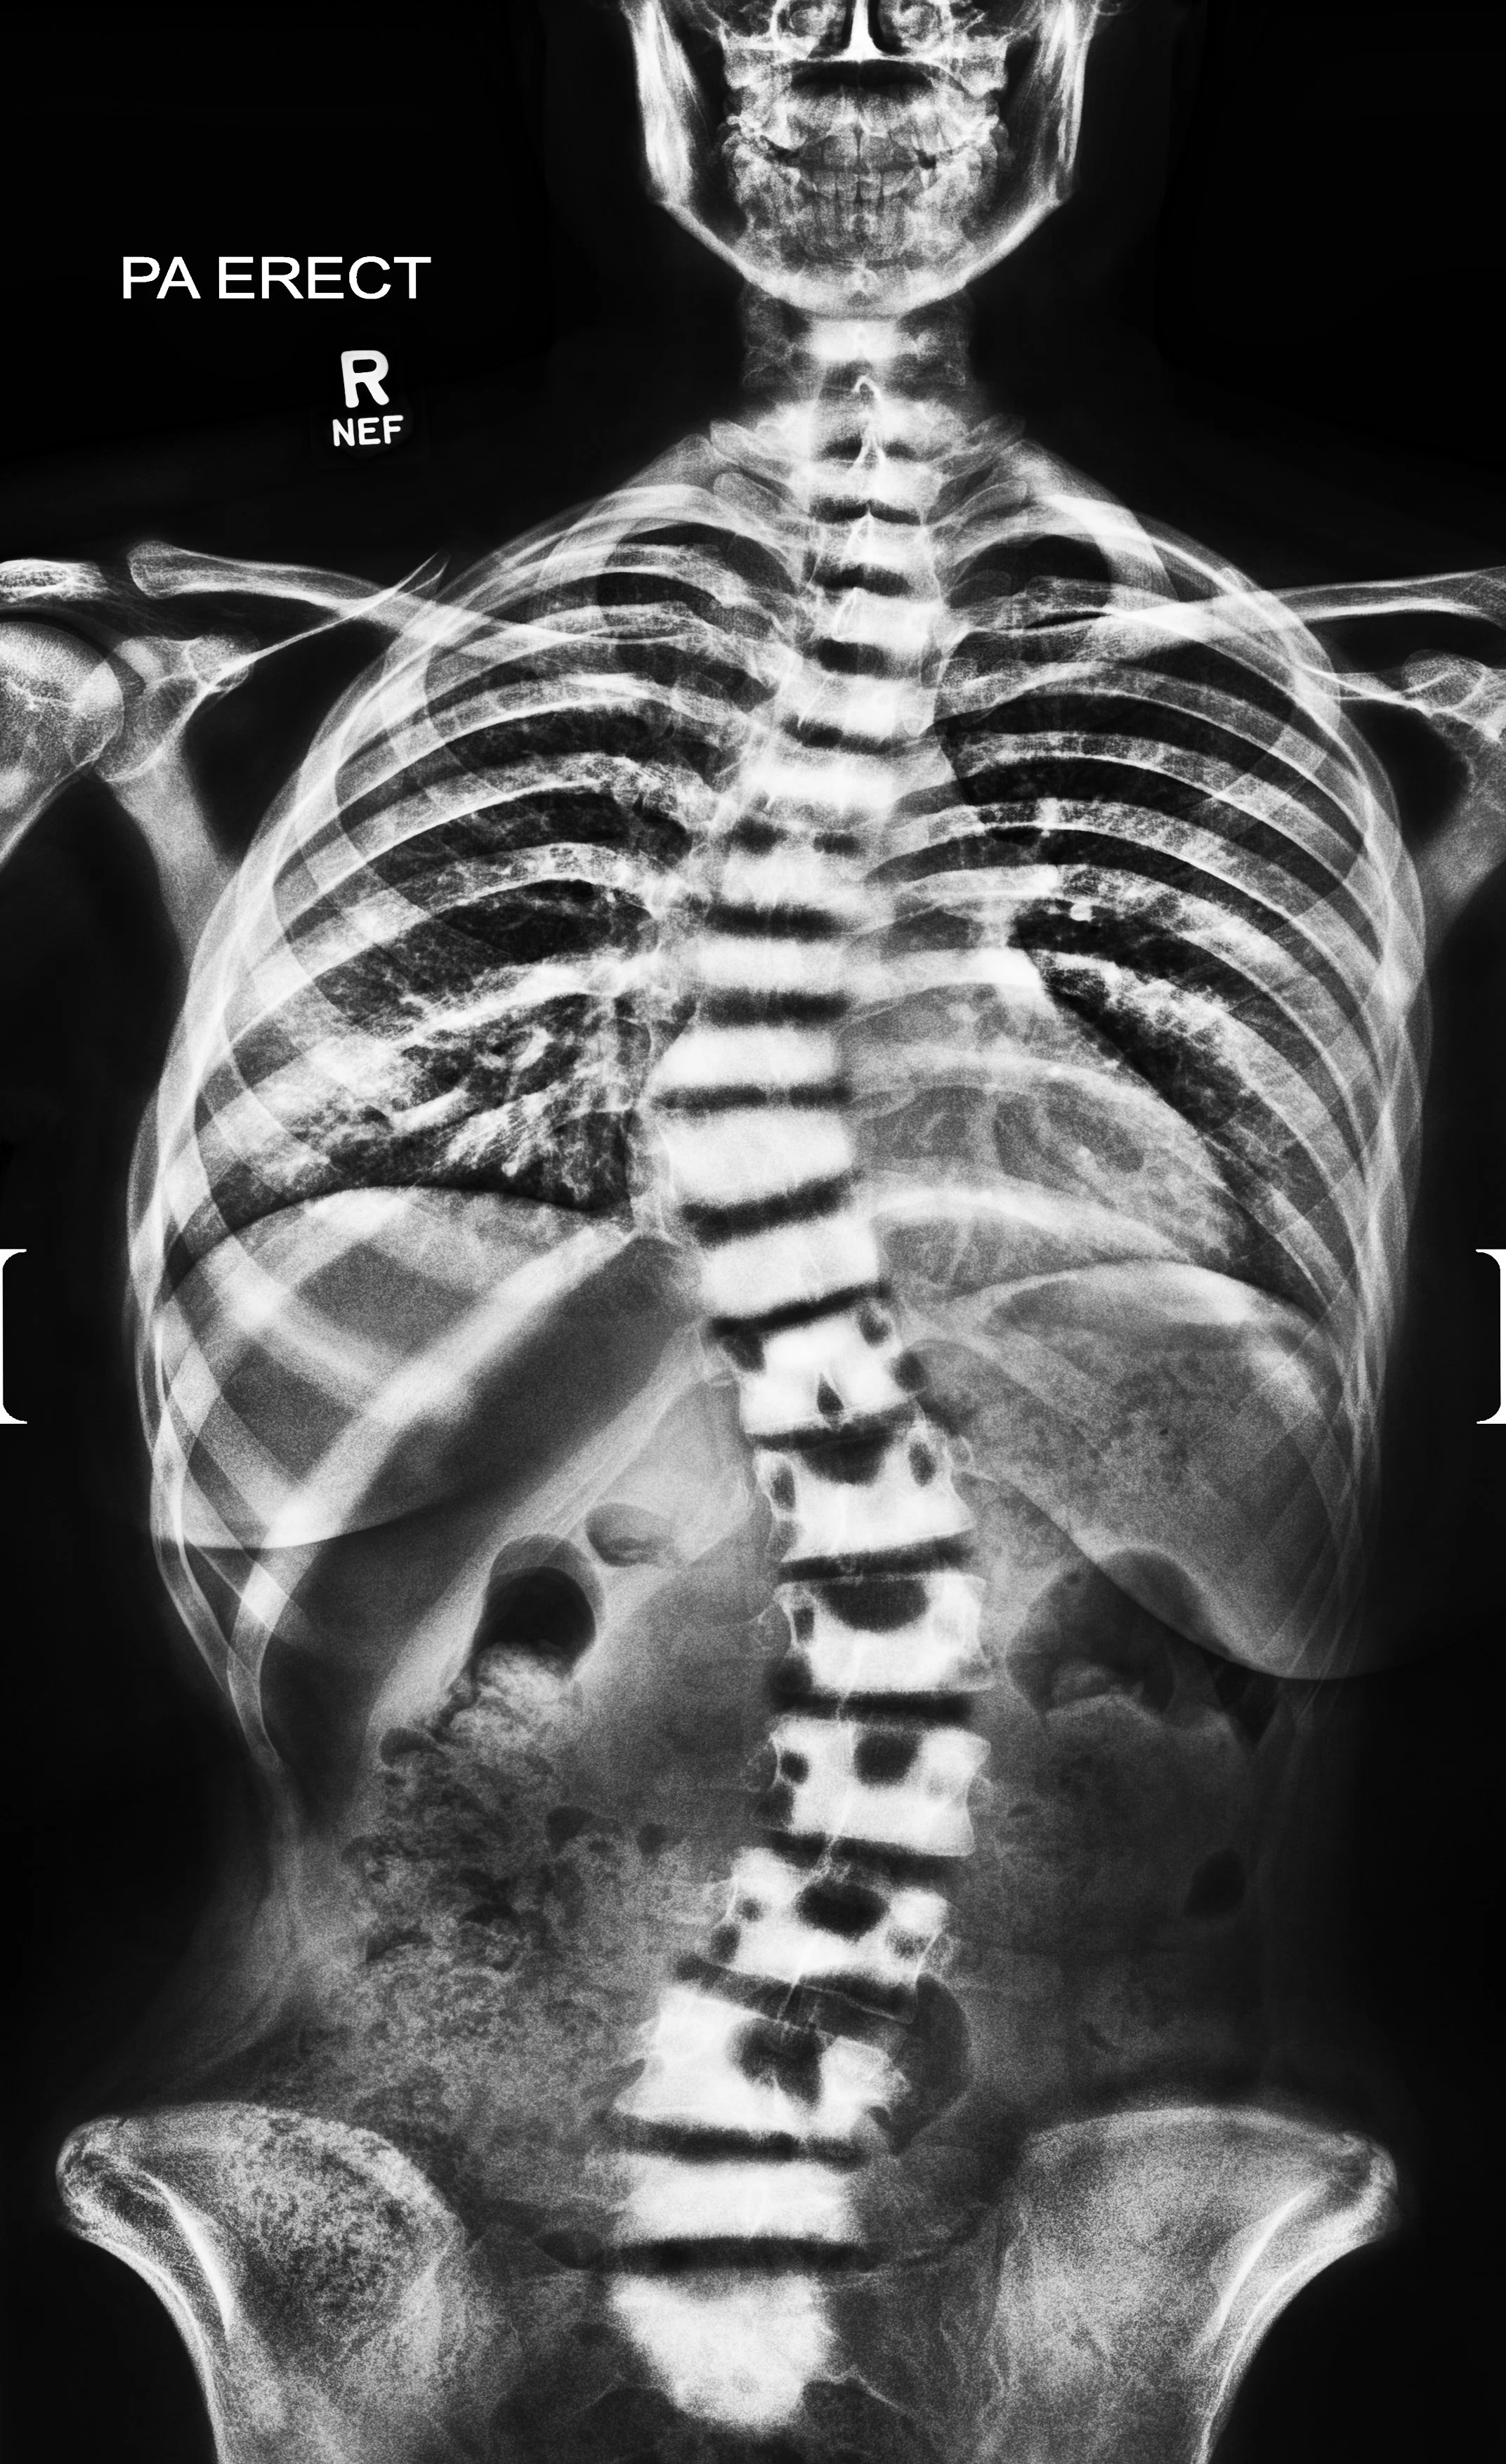

Defining Practice - 3D Scoliosis Spine